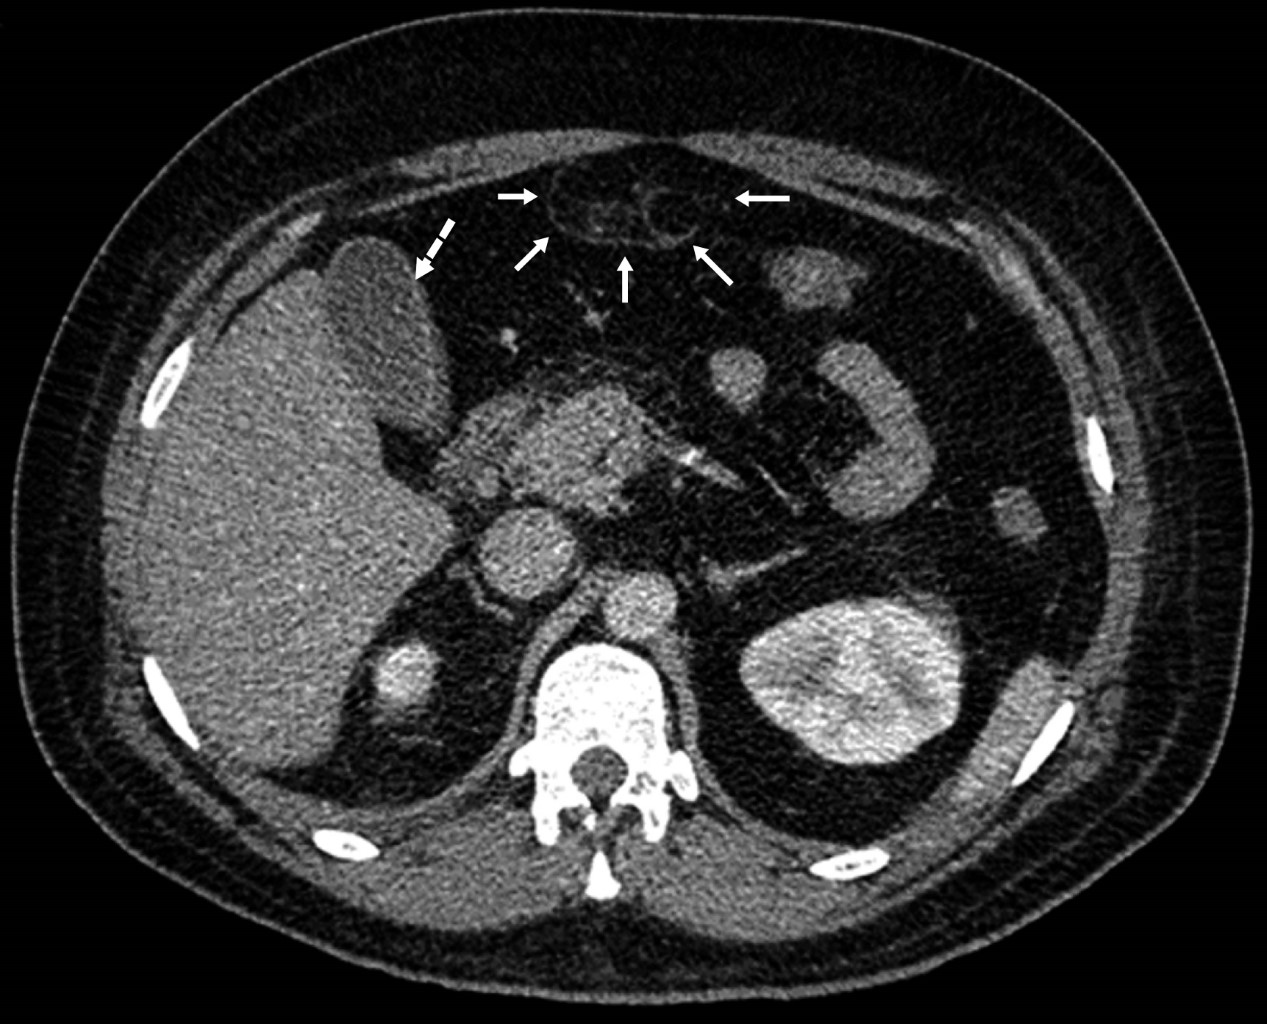

Se trata de paciente masculino de 34 años, inicia cinco días previo a su ingreso con dolor en fosa iliaca izquierda y dolor inguinal bilateral, acompañado de fiebre, escalofríos y diaforesis. A la exploración física a su ingreso presenta peristalsis disminuida, rigidez abdominal a la palpación y signo de Blumberg positivo. El laboratorio reportó: leucocitos de 15 × 109/L, hemoglobina de 15.6 g/dL, neutrófilos segmentados 11.54%, neutrófilos en banda 61%; examen general de orina (EGO): proteínas y cuerpos cetónicos presentes, leucocitos 2 × campo, bacterias escasas y sangre ausente. La tomografía computarizada abdominopélvica simple y con contraste IV mostró diverticulitis sigmoidea, Hinchey 1a (Figura 1). Cuatro días después manifiesta dolor abdominal irradiado a epigastrio, la tomografía de control simple y contraste IV (Figuras 2 y 3) mostró cambios inflamatorios en el recorrido completo del ligamento Teres, altamente sugestivos de trombosis, así como vesícula biliar reactiva (pared gruesa) y adenitis mesentérica, discreto líquido libre abdominal y derrame pleural bilateral. El paciente recibió tratamiento conservador y fue dado de alta al séptimo día.

Figura 2